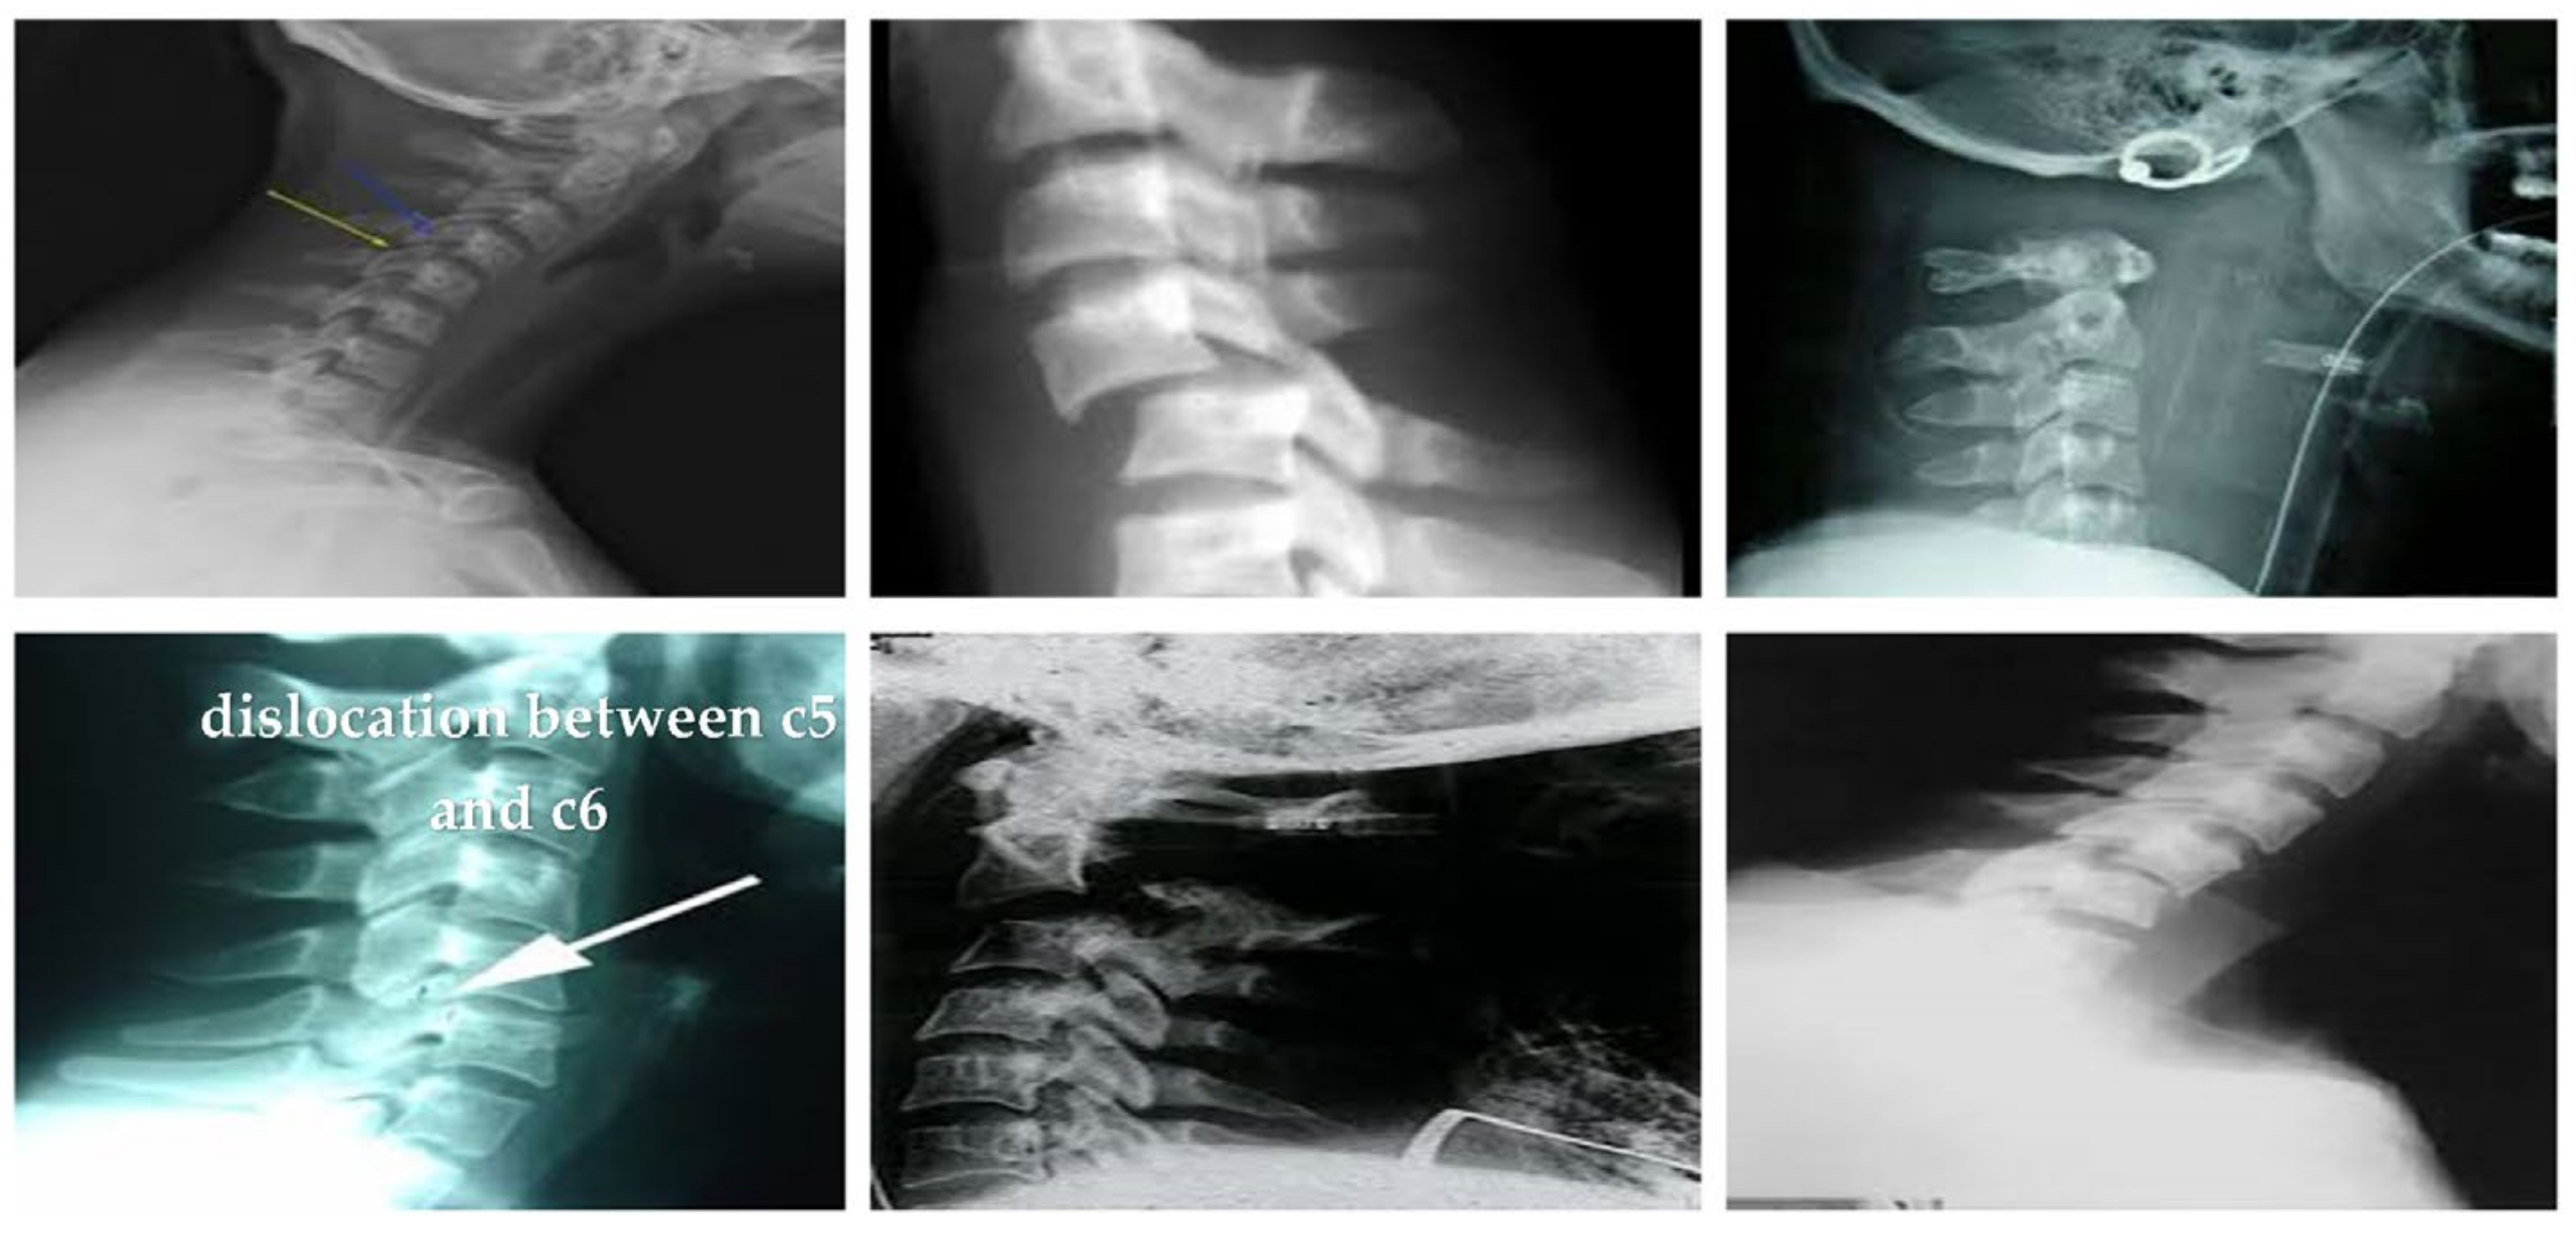

4.1.2. Clinical Case Study